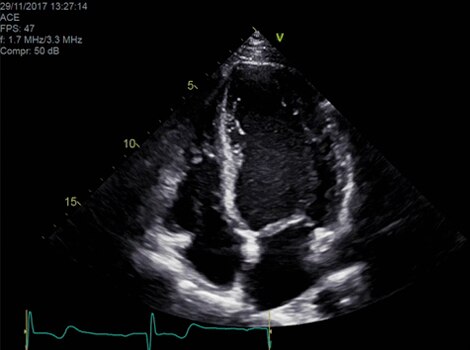

Vivid Family Cardiac Ultrasound with Auto EF

Assess left ventricular function and cardiac performance with clarity, improving clinical confidence.  Read More

VividTM Family Cardiac Ultrasound Automated Function Imaging (AFI)

Diagnosis typically involves assessment for ECG abnormality and assessment of cardiac structure, function and possible cause. Guidelines suggest use of echocardiography due to its widespread availability, but other non-invasive imaging modalities can be used. In certain cases, invasive monitoring provides useful information for patients with persistent symptoms. Biomarkers provide helpful information about progression of disease. 4